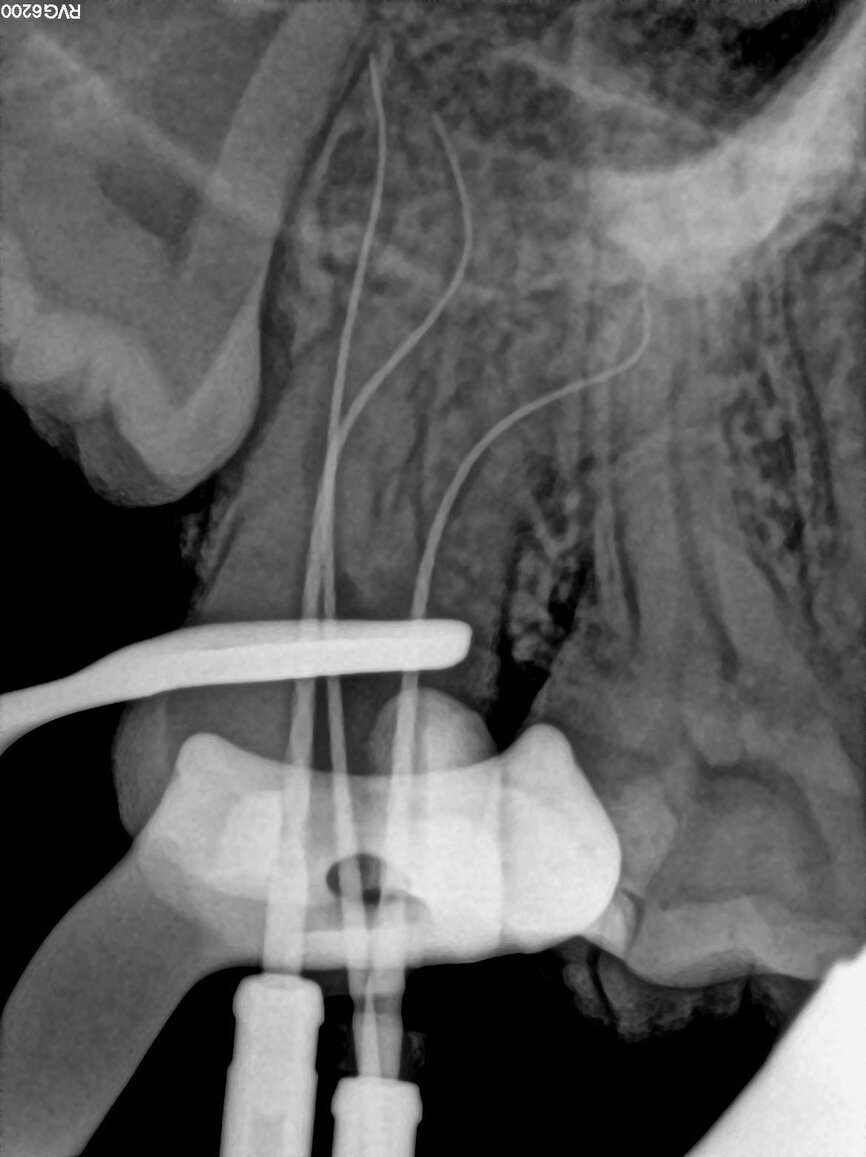

Fig. 20: Length determination radiograph.

The pulp chamber was filled with Glyde (Dentsply Sirona) before the canals were carefully negotiated to full working using pre-curved size 08 K-Files (Fig. 19). Working length measurements obtained from an electronic apex locator reading corresponded with the lengths obtained from the 3D Endo Software. These measurements were also confirmed radiographically (Fig. 20). A reproducible glide path was prepared in each root canal system with the size 08 K-File in an M4 Reciprocating handpiece (Sybron Endo; Fig. 21), followed by making a size 10 K-File ‘super loose’ (Fig. 22). A ProGlider (Dentsply Sirona) was used in a rotary motion to expand the glide path in the palatal root canal (Fig. 23). Considering the sharp and severe curvatures in the two buccal canals, it was decided to convert the ProGlider instrument into a manual file to expand the glide path in these tortuous canals with more safety (Fig. 24). The manually adapted ProGlider was used in a balanced force motion up to working length. In addition, to create more safety during the canal preparation of the two challenging buccal root canals, it was also decided to use the reciprocating WaveOne Gold Glider (Dentsply Sirona; Fig. 25), after the ProGlider instrument to further expand the glide paths. The WaveOne Gold Glider was used in 4–8 backstroke brushing motions from working length, in the two buccal root canal systems.